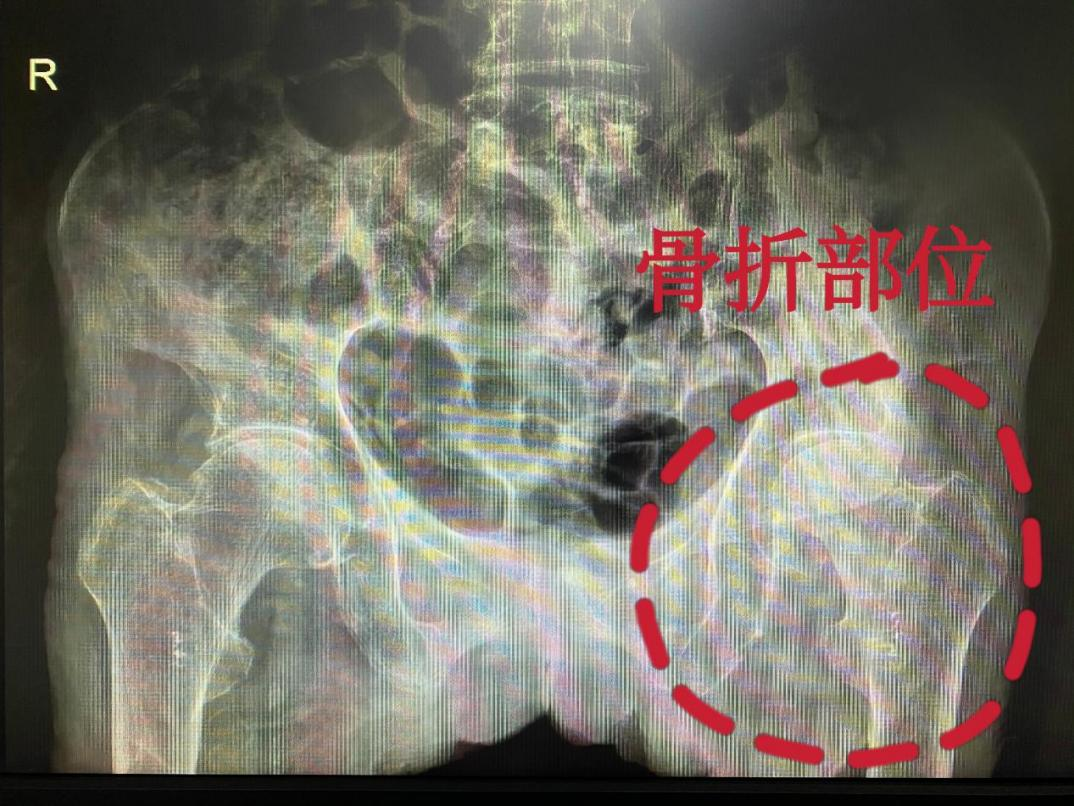

家住环江县明伦镇的莫奶奶已经100岁高龄,平时身体健康,生活能自理。2021年1月份因上厕所时不慎摔倒,卧床已两个月之久,后来通过邻居介绍转至我院脊柱骨病关节外科治疗,入院诊断:“左股骨颈骨折、低蛋白血症、低钾血症”,需要进行髋关节置换手术。

莫奶奶术前左股骨颈骨折X线检查影像图片